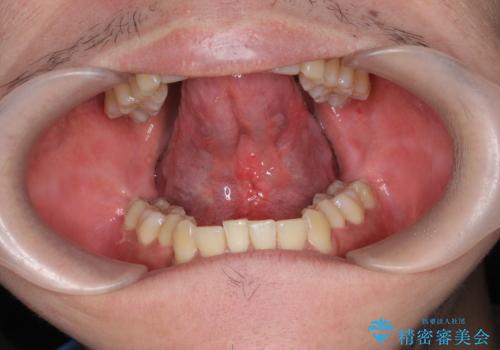

手術を受ける前は怖かったけれど、長年悩みの種であった滑舌が改善できたと喜んでいただくことができました。

- 外科手術のため、術後に出血、痛みや腫れ、違和感を伴います